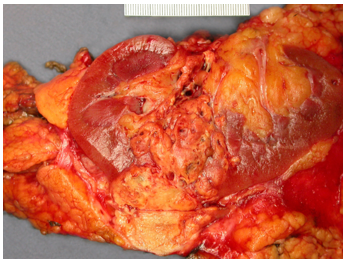

Hình 3. ccRCC có màu vàng, giới hạn ở thận (pT1b)

Thường là khối u vỏ thận một bên và đơn ổ, kích thước trung bình khoảng 7 cm. Khối u thường có ranh giới rõ, được bao quanh bởi giả bao u, phát triển theo kiểu đẩy nở và lồi ra từ vỏ thận. Hình thái đại thể đa dạng với thành phần đặc và nang, kèm các vùng xơ hóa màu xám và các ổ xuất huyết mới hoặc cũ màu nâu; hoại tử và biến đổi nang gặp thường xuyên. Khối u có màu vàng ánh kim do hàm lượng lipid cao; các khối u có độ mô học cao hơn có thể không có màu vàng do hàm lượng lipid và glycogen thấp hơn. Các vùng mềm, dạng thịt có thể phản ánh sự hiện diện của biệt hóa dạng sarcomatoid. Thường xuyên ghi nhận xâm lấn tĩnh mạch thận và xoang thận. Tổn thương hai bên và đa ổ là đặc điểm gợi ý bệnh lý di truyền.

Đại thể